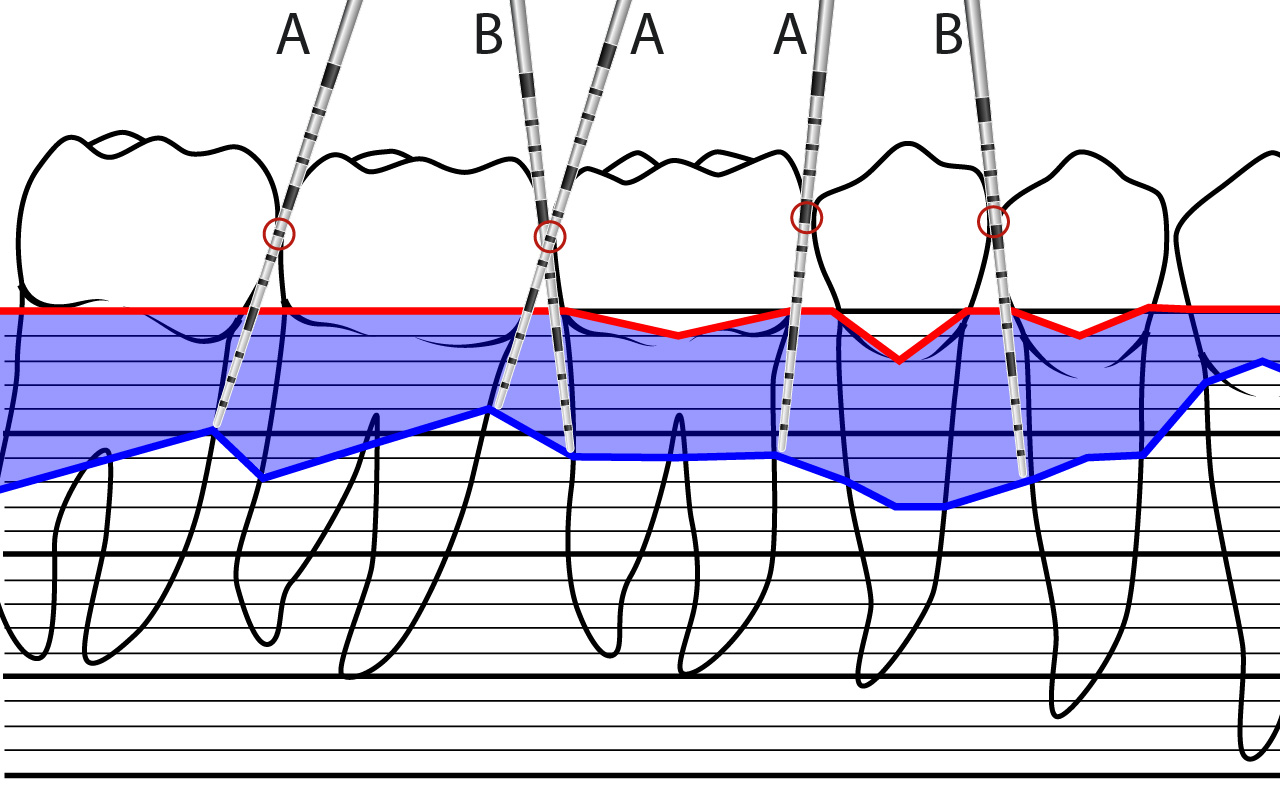

Anstellwinkel der Parodontalsonde

Bei der Messung der Sondierungstiefe wird die Sonde entlang der Zahnoberfläche nach apikal geführt. Dabei kann sie sich in mesio-distaler Achse neigen A resp. B, währenddem die bukko-orale Richtung parallel zur Zahnlängsachse gehalten werden muss.